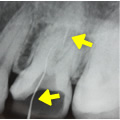

感染根管処置症例.2

主訴:前歯に違和感がある。

- 過去に根管治療を行っていたが、感染を起こし根の先に大きな膿の袋が出来ている。

- 再度根管治療を行い、根の内部から膿の袋に直接薬を作用させている。

- 根管充填剤が根尖(根の先端)まできっちりと充填されている。術前に存在した大きな膿の袋は消失してきている。